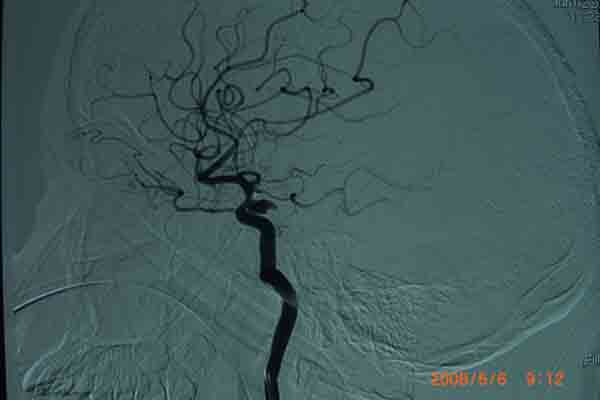

6月6日上午,在明州医院放射科的DSA检查室内。上海的神经外科专家及麻醉科在为一位38岁的云南来宁波打工中年女病人做颅内动脉瘤(眼颈交界处7*3.5cm)血管内栓塞手术。无影灯下,准备工作在有条不紊地进行着。全身麻醉后。介入手术开始了,手术医生以非常娴熟的手法,在右侧股动脉内置入导管,在显像下,随着导丝进入,顺利到达动脉瘤瘤腔内。随着弹簧圈进入,瘤腔内被充填。造影后,显示位置良好。所有的神经外科医生知道,在手术过程中,如果发生动脉瘤破裂,那后果不堪设想。手术成功了,大家悬着的心放下了。整个手术时间仅仅用了1个半小时。手术后,病人即清醒,送回病房。

回想这个病人是5月 20 日,因为在早晨起床后,突然昏迷不醒,跌到在地,被家人送往明州医院急症室,经过医生检查,这个病人已经瞳孔放大,呼吸停止。紧急地插入气管导管后,给予呼吸机使用。经过医院上海神经外科专家检查病人后,指出这是动脉瘤破裂出血导致的呼吸压制。需要头颅CT检查,在捏着皮球保持呼吸道通畅,即刻行头颅CT检查,确认为动脉瘤破裂出血,前交通动脉瘤破裂为主。专家看了片子后,认为如果行双侧脑室外引流,将血液引出,可能会使呼吸恢复。马上送手术室做急症手术,引流出血性脑脊液后,病人呼吸慢慢恢复了。经过3个星期的正规治疗(高血压,高颅压,高体温)(抗血管痉挛,抗感染)(外引流)病人终于度过了危险期。在6月6日上午成功进行了颅内动脉瘤血管内栓塞手术。